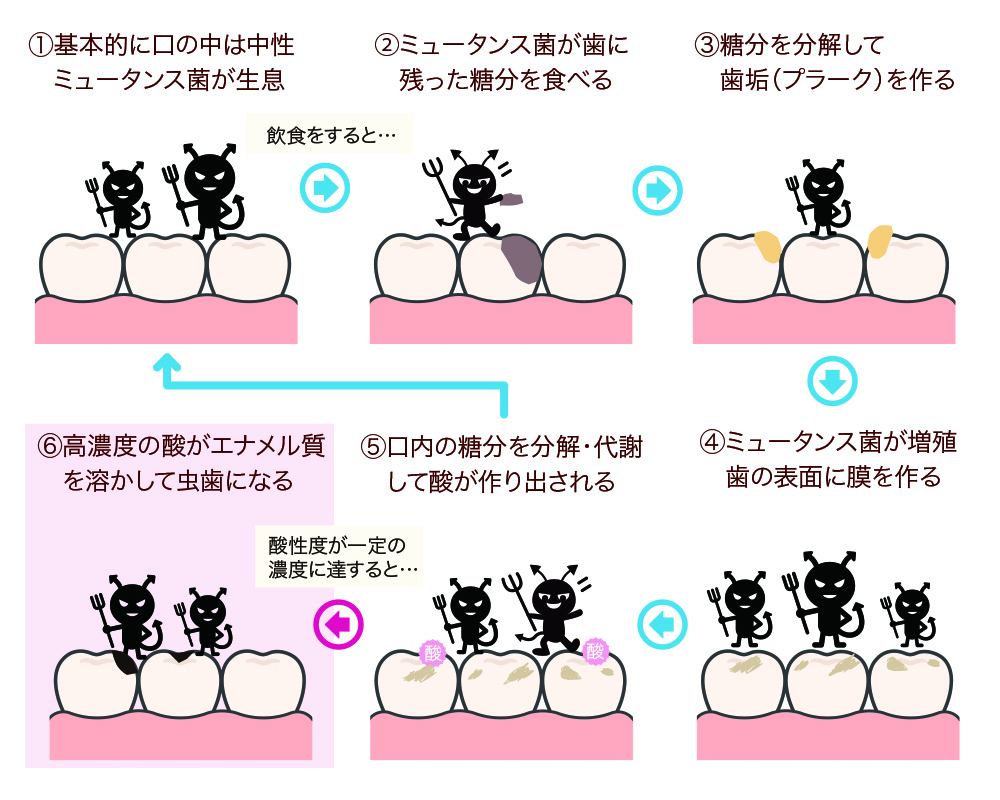

虫歯ができるまでの流れ

虫歯の原因は、細菌が繁殖したかたまりである歯垢(プラーク)で、主な原因菌はプラークの中にいるミュータンス菌です。ミュータンス菌は多くの人の口の中に常在しており、糖分を栄養にして増殖します。そして、飲食などによって口内に残った糖分を餌にして「乳酸」などの強力な酸を作り出し、歯のエナメル質を溶かします。